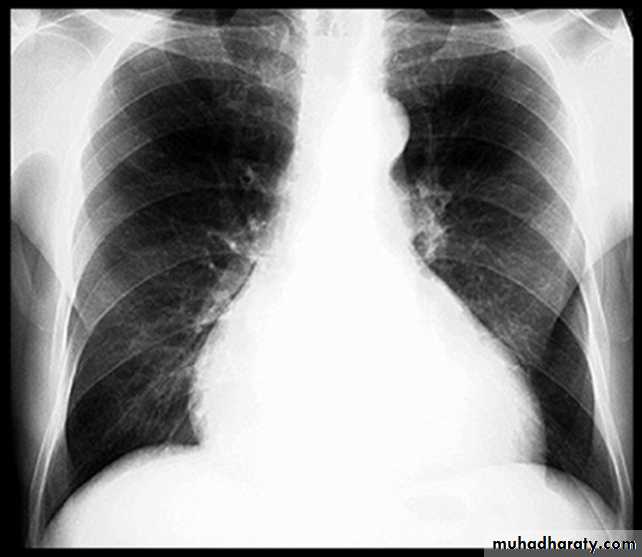

BNP brain natriuretic pepetideChest X-ray in Heart Failure

CardiomegalyCephalization of the pulmonary vessels

Kerley B-lines

Pleural effusions

Cardiomegaly Pulmonary vessel congestion